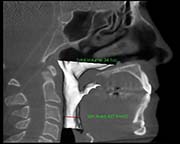

3 months post surgery

Surgical Plan